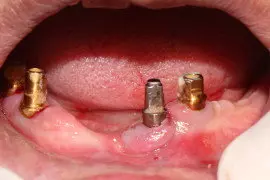

Peri implantitis

A Serious Complication in Implant Dentistry

Peri-implantitis is infection of supporting tissues around dental implants like bone, gingiva & oral mucosa.

It is a very serious complication, and may lead to total failure of implant & other major bone related complications.

Peri-implantitis is not only common, but a serious complication. Implants have the potential to last a patient’s entire life. Peri-implantitis can lead to disintegration and early loss of implant and their supported prosthesis

Treatment of peri-implantitis include antibacterial therapy along with localised cleaning & also dental lasers are useful in treatment of infection around dental implants.